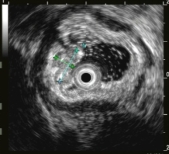

大型超声内镜下(EUS)胰腺占位性病变的FNA/FNB技术

胃内粘膜下隆起,术前结合我科超声内镜,诊断考虑异位胰腺。

胃内粘膜下隆起,术前超声提示来源于固有肌层,术前判断需胃壁全层切除。

术中所见与术前判断相符,行内镜全层切除术EFTR,术后严密封闭创面,患者2日后安全出院,术后病理诊断胃间质瘤。